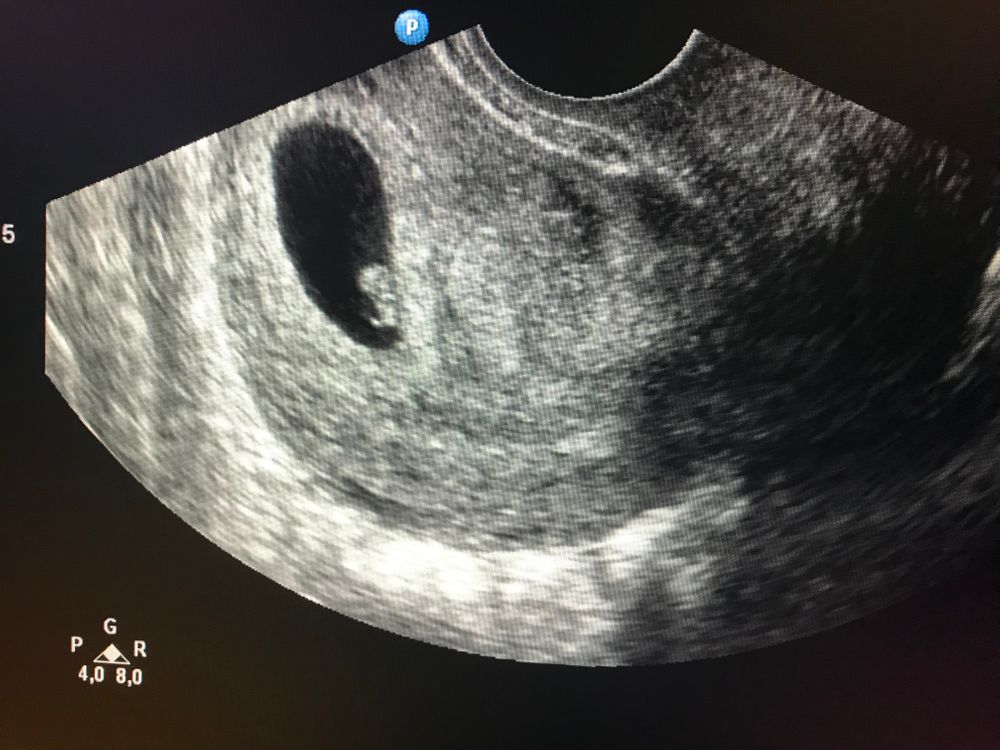

Девочки подскажите пожалуйста может кто с таким сталкивался, вчера сделала первое узи срок 5 недель. Но плод не увидели и поставили ещё в заключении «Ретрохориальную гематому» может кто нибудь с таким сталкивался. Гинеколог сказала ждём ещё неделю, либо плод увидят либо это замершая беременность. Вчера весь день была на панике…

В 5 недель у меня только плодное яйцо было, какой эмбрион, через неделю все уже будет, не переживайте🙃

У меня в 5 нед было пя 5 мм, ну какой там эмбрион 🤦♀️ Чего они хотят, я вообще не понимаю, столько постов именно таких как ваш. Ждите! В 7 нед все будет 👌

узи делала на 5 неделе , плода тоже не было. Врач сказала «ребятенок появится к 7 неделе», я спокойно подождала пару недель и пошла на УЗИ.

Плод уже был виден, просто рано ещё , не переживайте.